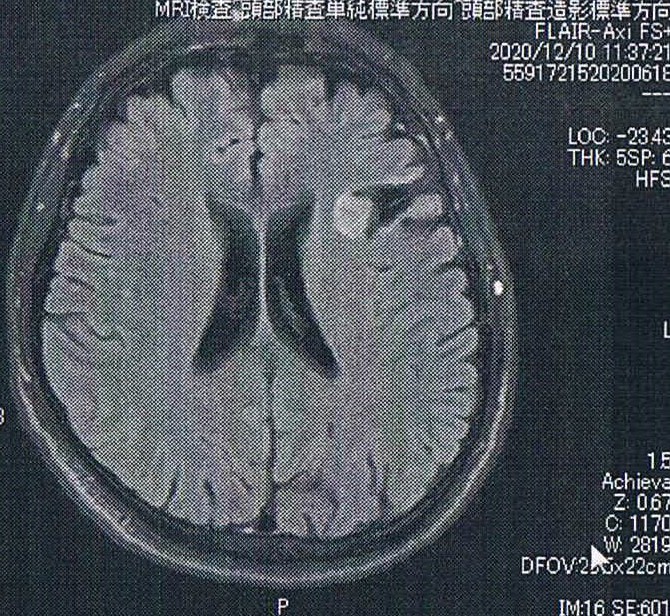

悪性転化しやすい腫瘍の種類(びまん性星細胞腫グレード2)であるとのことで造影剤を注射してMRI検査をする。手術から6.5年が経過した。

診断の結果は特に変化はなく問題なし。造影剤がしみ込んでいる箇所もないとのことで、悪性度は低い状態を保っているとのこと。これは前回から変わらず、まずはホッとした。